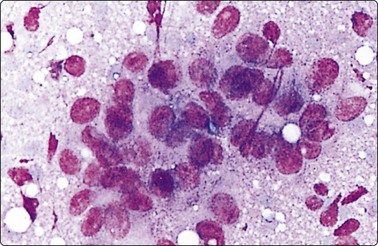

image image

Fig. 5.6 Reactive lymphadenopathy

(A) Smear derived from germinal center; loose tissue fragment of dendritic reticulum cells with ovoid nuclei and granular chromatin, centroblasts, centrocytes and some lymphocytes; syncytial background of pale cytoplasm; (B) Mixed population of lymphoid cells; two nuclei of dendritic reticulum cells with granular chromatin and small distinct nucleoli lower mid (MGG; HP).